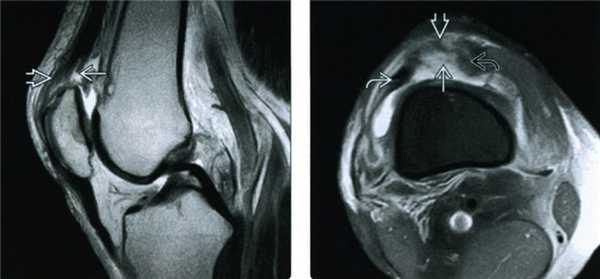

Помимо специально подготовленных вопросов и обследования, рентген помогает специалисту Геленк Клиники исключить наличие костных повреждений. В данном случае необходимо учитывать не только переломы, но и разрывы с костными фрагментами либо травмы межберцового синдесмоза (костное сращение из соединительной ткани). Так как рентгенологическое исследование показывает состояние костных структур, но не отображает связки, мы рекомендуем сделать так называемый удерживаемый снимок, где врач обследует расслоение суставной щели по сравнению с противоположной стороной. Таким образом можно отличить простое растяжение от разрыва. Подобные записи изготавливаются при помощи специального опорного аппарата и стандартного осуществления давления. В отдельных случаях проводится дополнительное обследование. Пациента направляют на МРТ либо УЗИ. Эти методики могут также выявить и травмы мягких тканей.

Необходимо приложить холод и зафиксировать поврежденный сустав, затем обратится в лечебное учреждения, где вам выполнят рентгенографию голеностопного сустава. Часто этого бывает недостаточно и может потребоваться ряд дополнительных обследований, таких как ультразвуковое исследование сустава, магнитно-резонансная томография (МРТ) для оценки состояния мягкотканых структур (связок, сухожилий) голеностопного сустава.